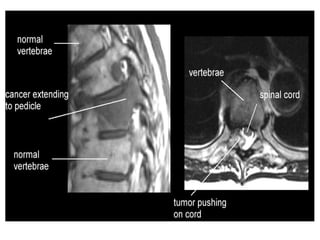

MRI – hypodense in T1;doesnot cross the adjacent

disc space